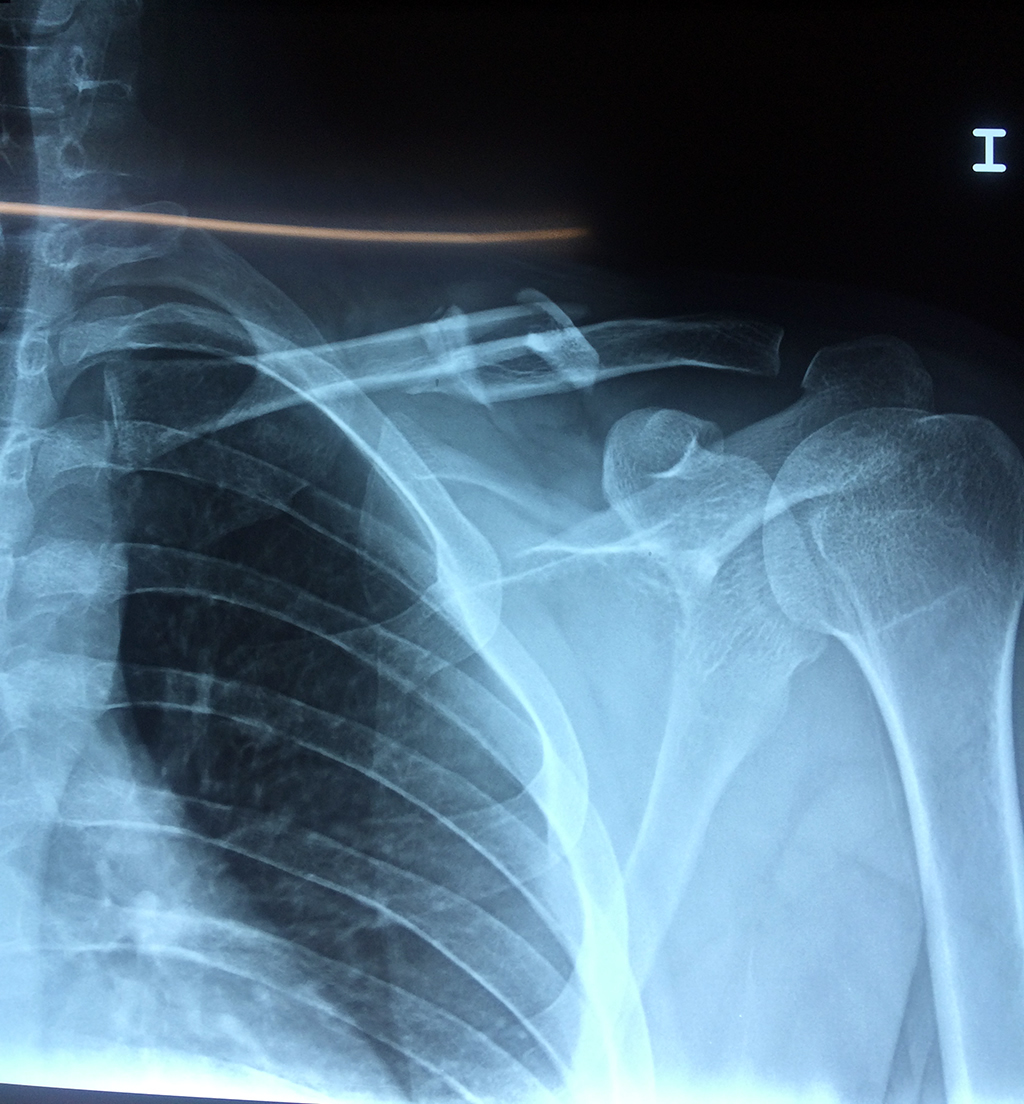

Cirugías de Codo - Clavícula

La clavícula es un hueso largo, con forma de "S" itálica, situado en la parte anterosuperior del tórax. Junto con la escápula forman la cintura escapular. Se puede palpar por toda su longitud y se extiende del esternón al acromion de la escápula, siguiendo una dirección oblicua lateral y posterior.